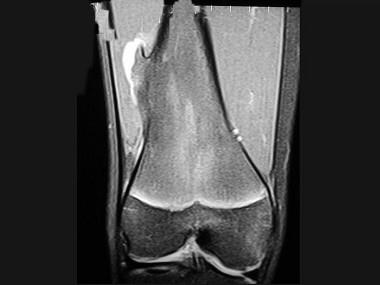

问题 男,13岁,运动后膝痛,请结合影像图像,选择最可能的诊断 ( )

选项 A、成骨细胞瘤 B、骨样骨瘤 C、动脉瘤样骨囊肿 D、骨软骨瘤 E、正常影像

答案 D